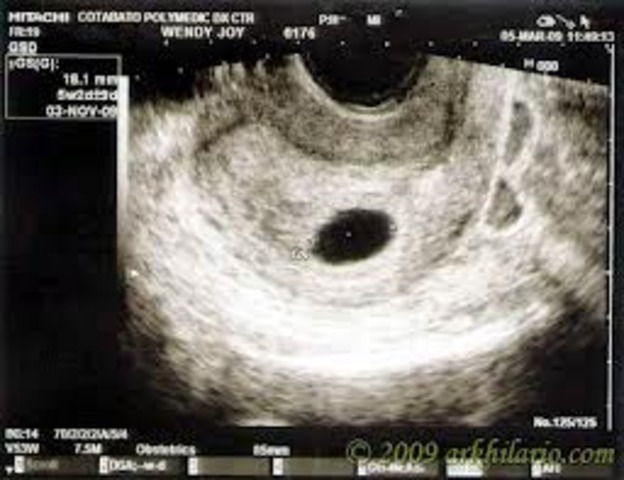

Month 1

Mom: Missed a period.

Baby: size of pin head.